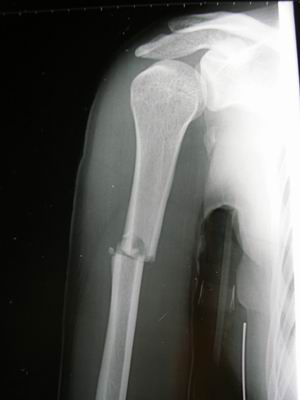

肱骨干骨折

开始有些愈合的骨痂了